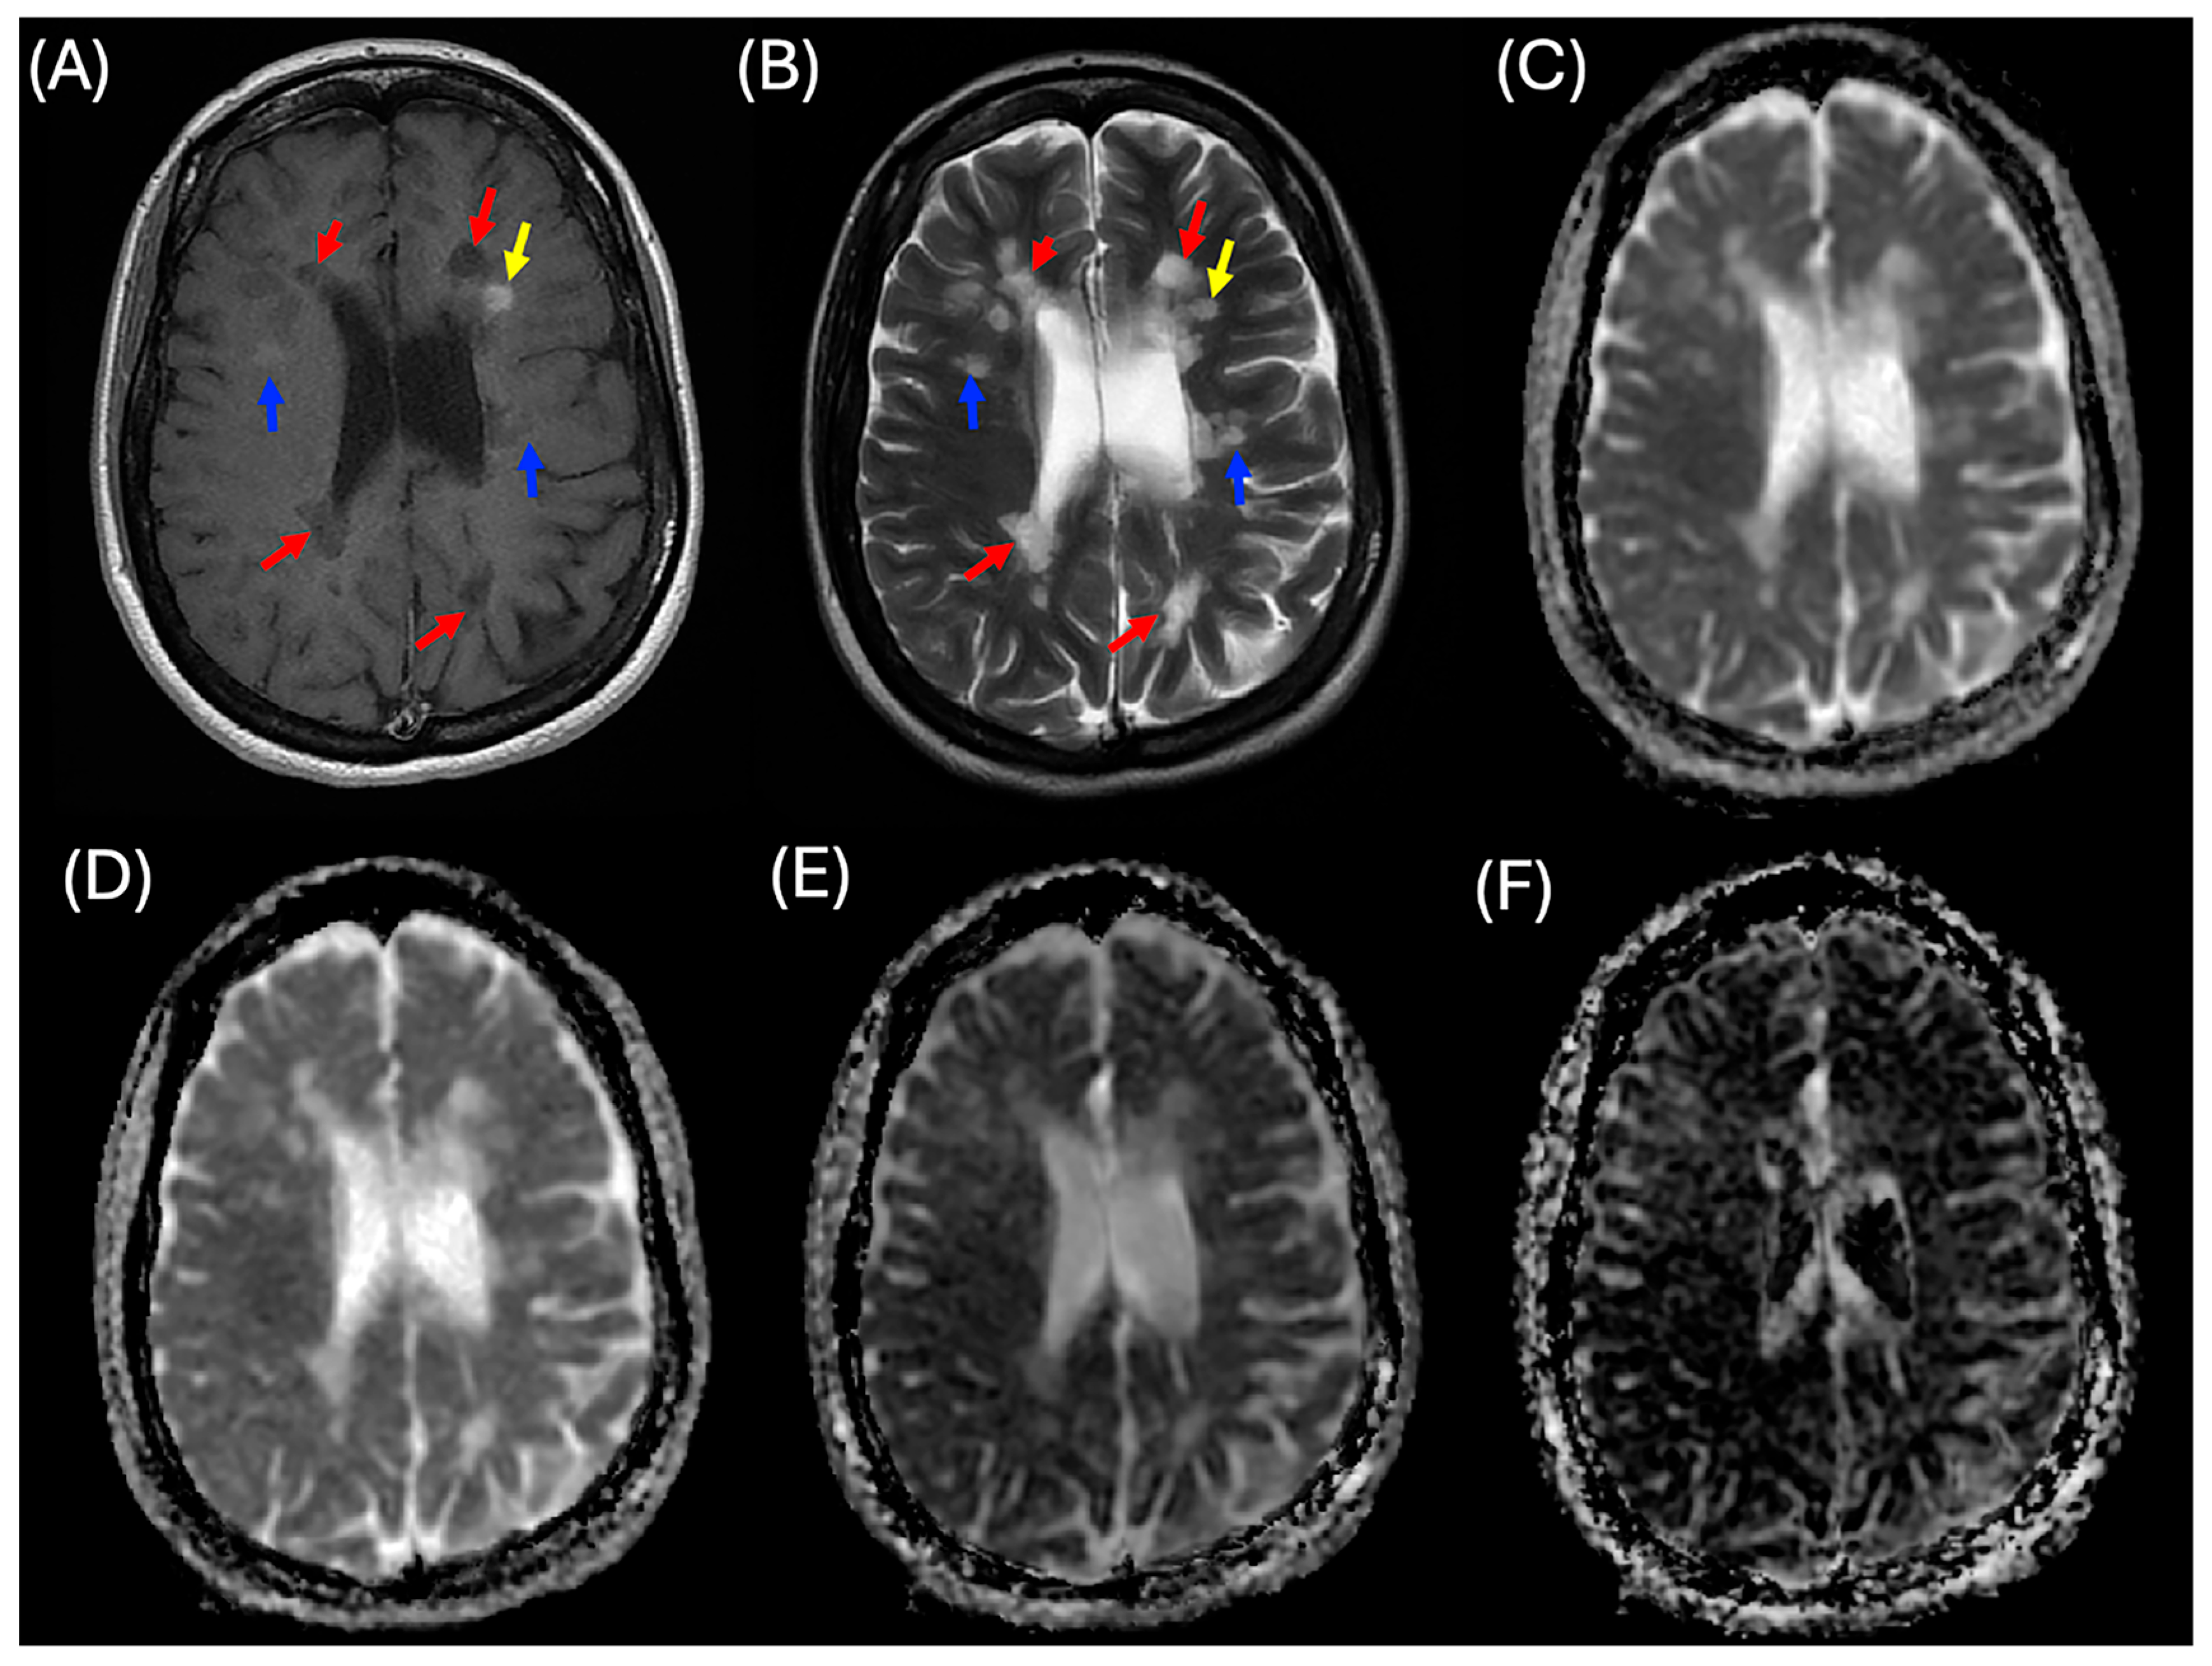

Three MS lesion patterns were analyzed, including enhanced, non-enhanced, and black holes, as shown in Figure 1. MS enhanced (MS_E) lesions were identified as hyperintense on post-contrast T1WI and hyperintense on T2WI. These lesions were observed in 42 patients with MS, with a total of 114 lesions. MS non-enhanced (MS_NE) lesions appeared isointense on both pre- and post-contrast T1WI and hyperintense on T2WI, with 1613 lesions identified across all patients with MS. MS black hole (MS_BH) lesions were characterized by hypointensity on both pre- and post-contrast T1WI and hyperintensity on T2WI, totaling 779 lesions. Of these, 119 black hole lesions were found in patients with enhanced lesions, while 660 were identified in patients with non-enhanced lesions.

Figure 1. A case of a patient with relapsing-remitting multiple sclerosis (MS) illustrating three categories of MS lesions. (A) Two-dimensional (2D) post-contrast T1-weighted imaging (T1WI), (B) 2D T2-weighted imaging (T2WI), (C) apparent diffusion coefficient (ADC) map, (D) diffusion coefficient (D) map, (E) pseudo-diffusion coefficient (D*) map, and (F) perfusion fraction (f) map. Yellow arrows indicate enhanced MS lesions, blue arrows indicate non-enhanced MS lesions, and red arrows indicate black hole lesions.